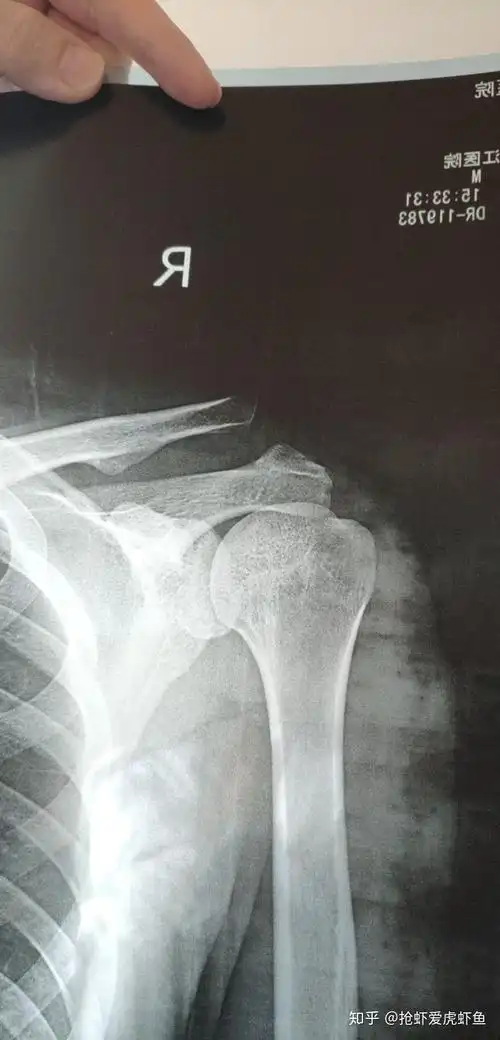

陈旧性肩锁关节脱位

相关图片